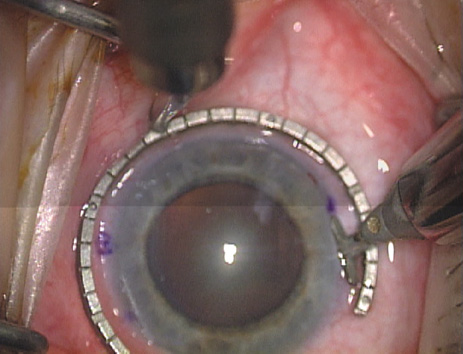

Case 2 is a 79-year-old woman who presented with a very dense left cataract. Her refraction was recorded at −2.25 +2.75 × 125 with a difficult end point. Her manual keratometry and topography measurements were consistent and revealed slightly less than 1.75 D at 120 degrees. Because of the questionable refraction, greater value was placed on the corneal measurements. Based upon the cataract nomogram, the plan was for paired LRIs of 40 degrees to be placed over the steep 120-degree axis (Figs. 1219).

Fig. 15. Total arc length equals 40 degrees. (Reprinted from Hardten DR, Lindstrom RL, Davis EA. Phakic Intraocular Lenses: Principles and Practice. Thorofare, NJ: SLACK Incorporated, 2004, with permission.)

Fig. 16. The starting point of the opposing incision is determined. (Reprinted from Hardten DR, Lindstrom RL, Davis EA. Phakic Intraocular Lenses: Principles and Practice. Thorofare, NJ: SLACK Incorporated, 2004, with permission.)

Fig. 17. The opposing incision is begun. (Reprinted from Hardten DR, Lindstrom RL, Davis EA. Phakic Intraocular Lenses: Principles and Practice. Thorofare, NJ: SLACK Incorporated, 2004, with permission.)

Fig. 18. The incision is completed. (Reprinted from Hardten DR, Lindstrom RL, Davis EA. Phakic Intraocular Lenses: Principles and Practice. Thorofare, NJ: SLACK Incorporated, 2004, with permission.)

Fig. 19. The temporal single-plane clear corneal incision is placed independent of the LRIs. (Reprinted from Hardten DR, Lindstrom RL, Davis EA. Phakic Intraocular Lenses: Principles and Practice. Thorofare, NJ: SLACK Incorporated, 2004, with permission.)